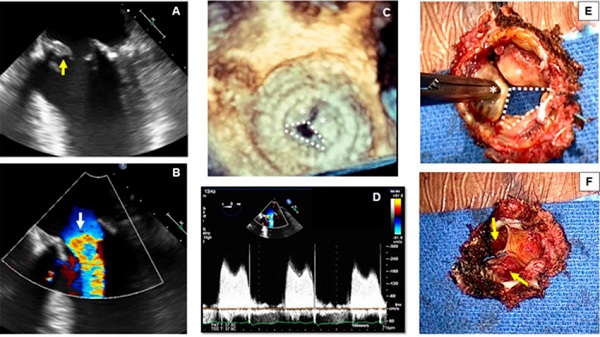

Una mujer de 70 años con antecedentes médicos de hipertensión, nefropatía crónica y sustitución de la VM por una válvula bioprotésica St. Jude Epic de 29 mm tres años antes se presentó con disnea de esfuerzo progresiva, opresión torácica y palpitaciones. Se descartó infarto agudo de miocardio sin elevación del segmento ST, según las guías. 9 Debido a la mala ventana acústica, se realizó un ETE.

En la vista medioesofágica de 4 cámaras se observa una apertura restringida de la bioprótesis de la VM y una estructura hiperecogénica adherida a la cara ventricular de las valvas de la bioprótesis (Fig. 4A, flecha amarilla). En la ecografía Doppler color se evidencia aceleración del flujo hacia la entrada de la VM (Fig. 4B, flecha blanca). En la imagen 3D ampliada de la bioprótesis de la VM se puede visualizar el movimiento restringido de dos de las valvas (Fig. 4C, asteriscos blancos) y la apertura completa únicamente de una valva (Fig. 4C, líneas blancas discontinuas). El gradiente transmitral medio de 12 mmHg en la ecografía Doppler pulsada indica estenosis mitral grave (Fig. 4D). Una vez retirada la bioprótesis, el cirujano comprueba el movimiento restringido de dos de las valvas (Fig. 4E, asteriscos blancos) y el movimiento conservado de solo una (Fig. 4E, líneas blancas discontinuas). Cuando se observa la bioprótesis extirpada desde su cara ventricular, se aprecia la presencia de trombos organizados que afectan ambas valvas inmóviles (Fig. 4F, flechas amarillas).

Objetivos de aprendizaje: Se debe sospechar de trombosis de la VM bioprotésica cuando hay restricción de movimiento de las valvas protésicas. En los pacientes que presentan insuficiencia cardíaca, gran carga de coágulos (>0,8 cm2) o enfermedad coronaria, en particular cuando la fibrinólisis está contraindicada, se prefiere la cirugía. 11 El análisis del eco 3D de la VM desde la perspectiva del cirujano (vista desde la aurícula izquierda) proporciona información adicional para el diagnóstico. La reconstrucción multiplanar del eco 3D también se puede utilizar para visualizar mejor la trombosis desde múltiples planos anatómicos.